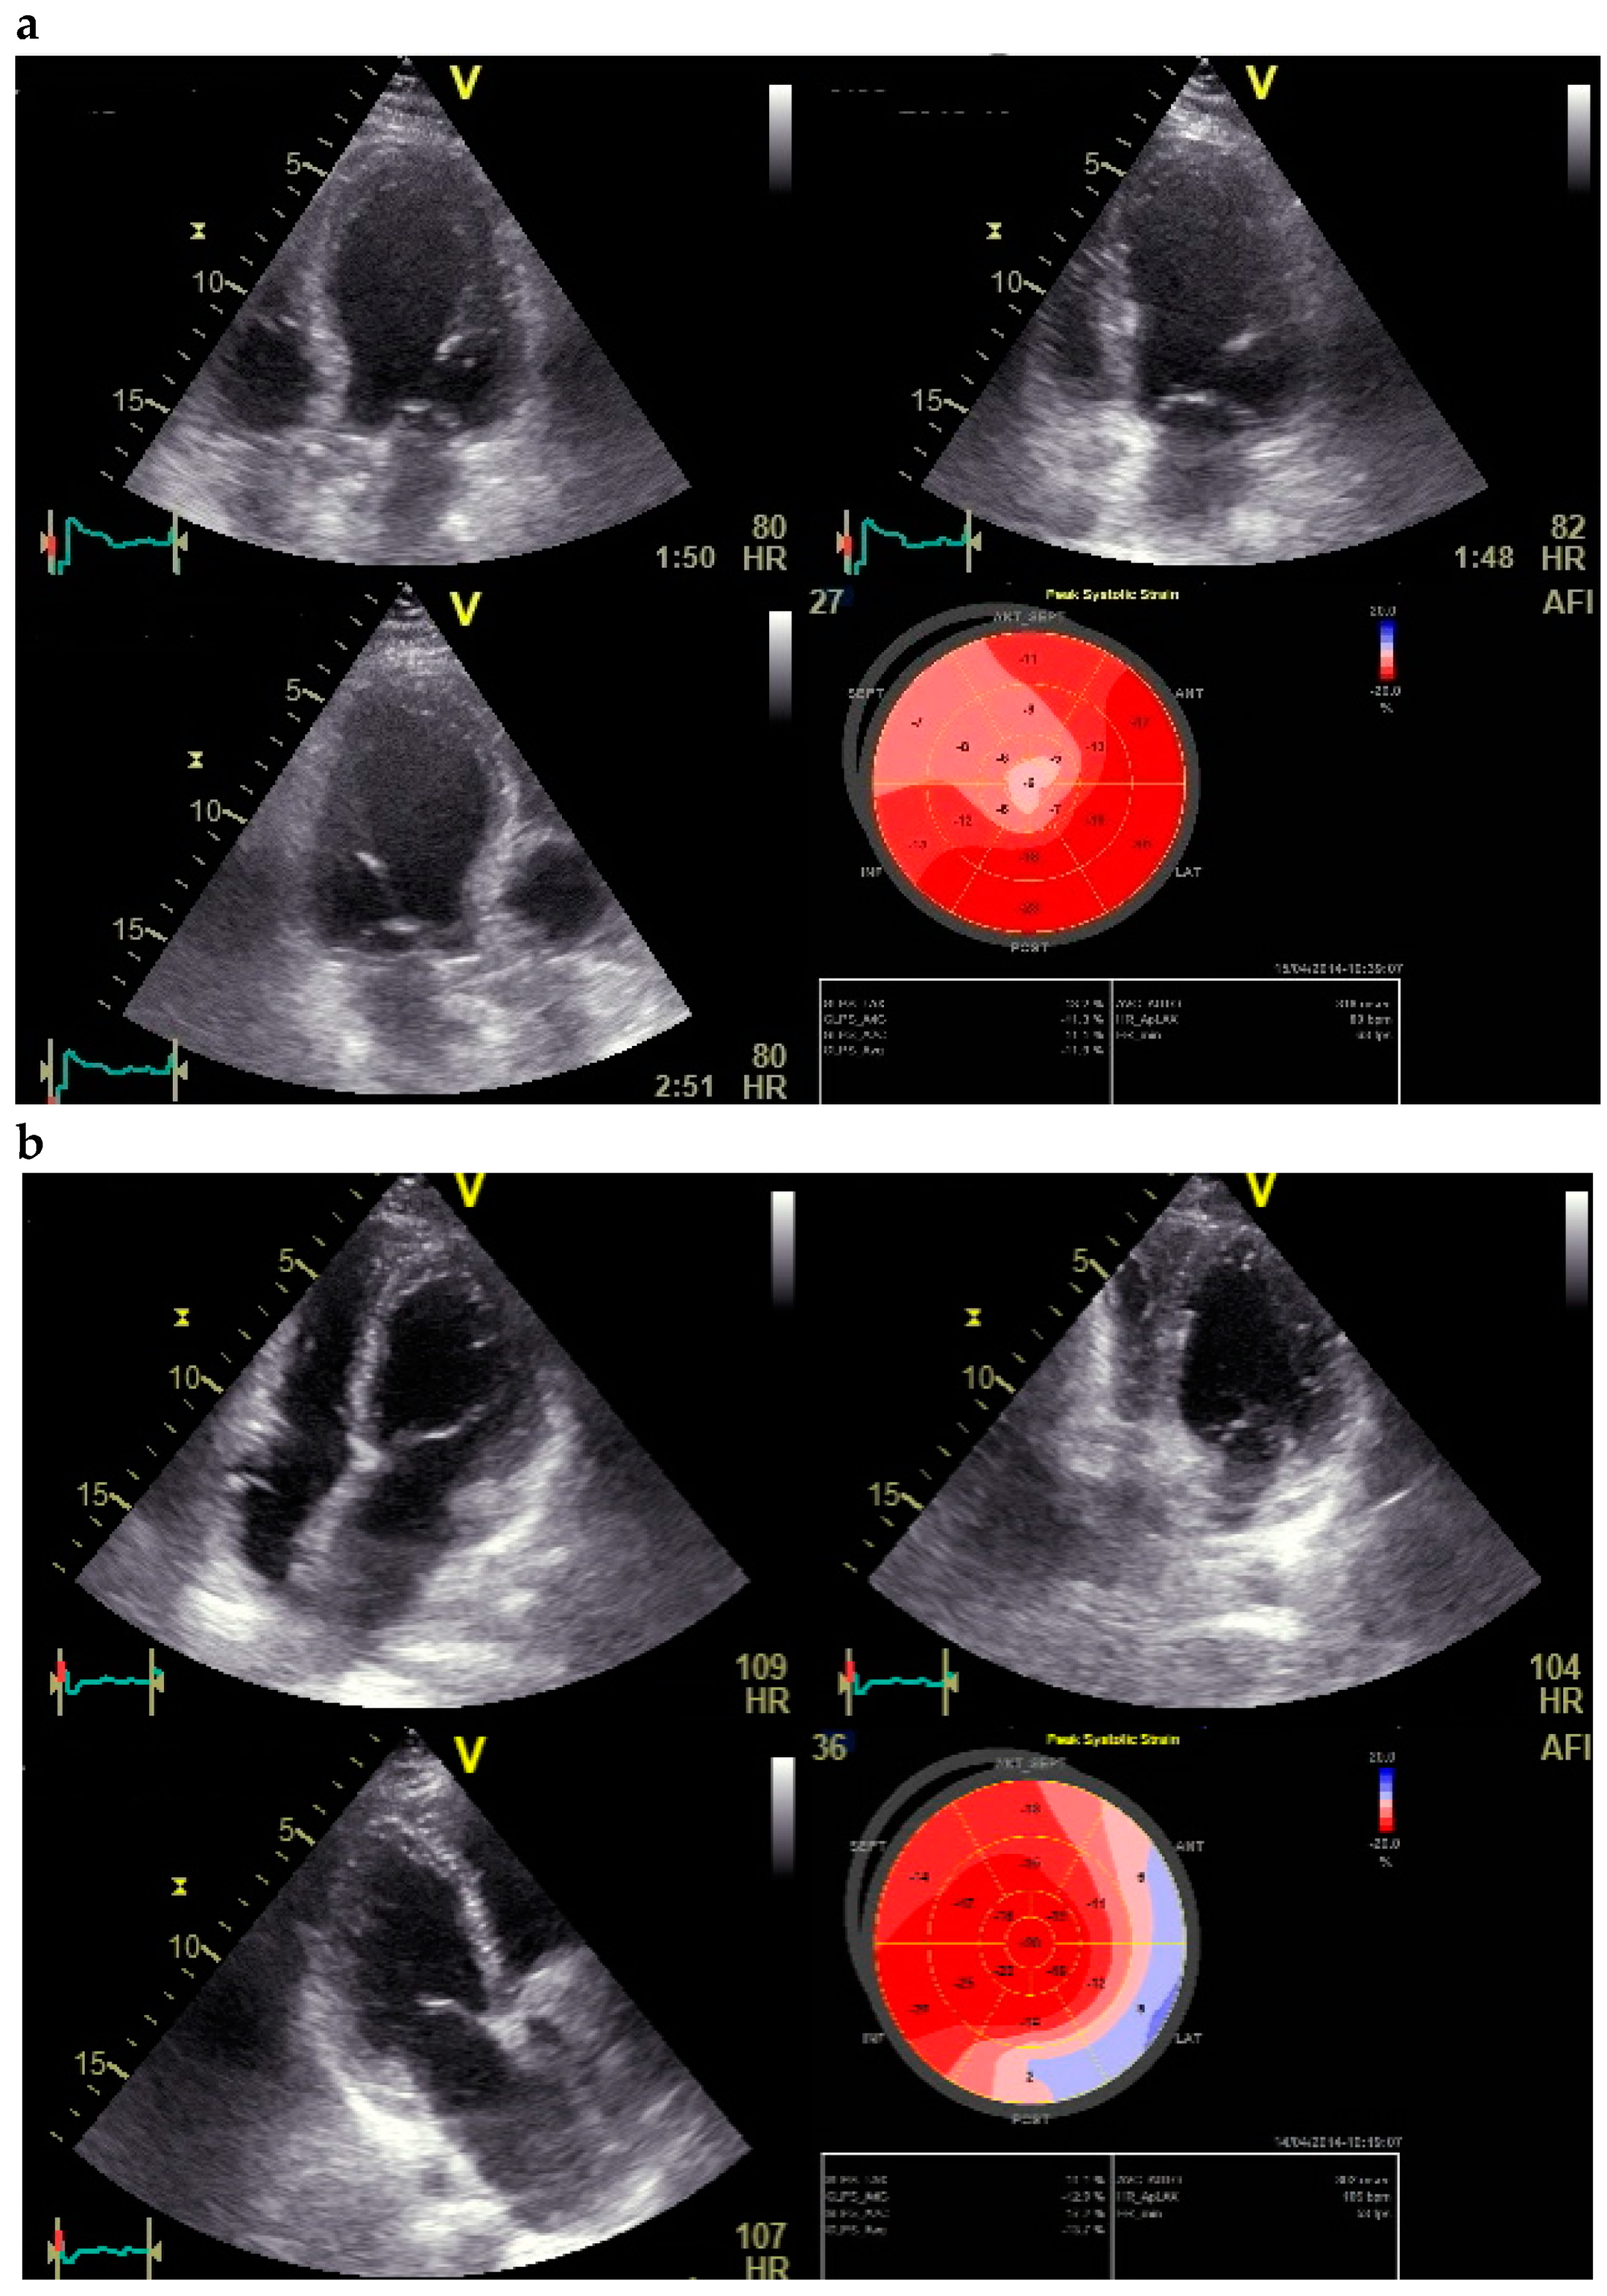

2.1. Echocardiography

2.2. Dobutamine Echocardiography

2.3. Quantification of Strain Measurements